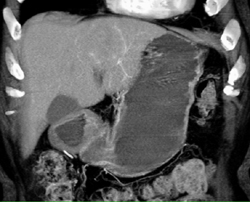

Diagnosis

Hepatoma